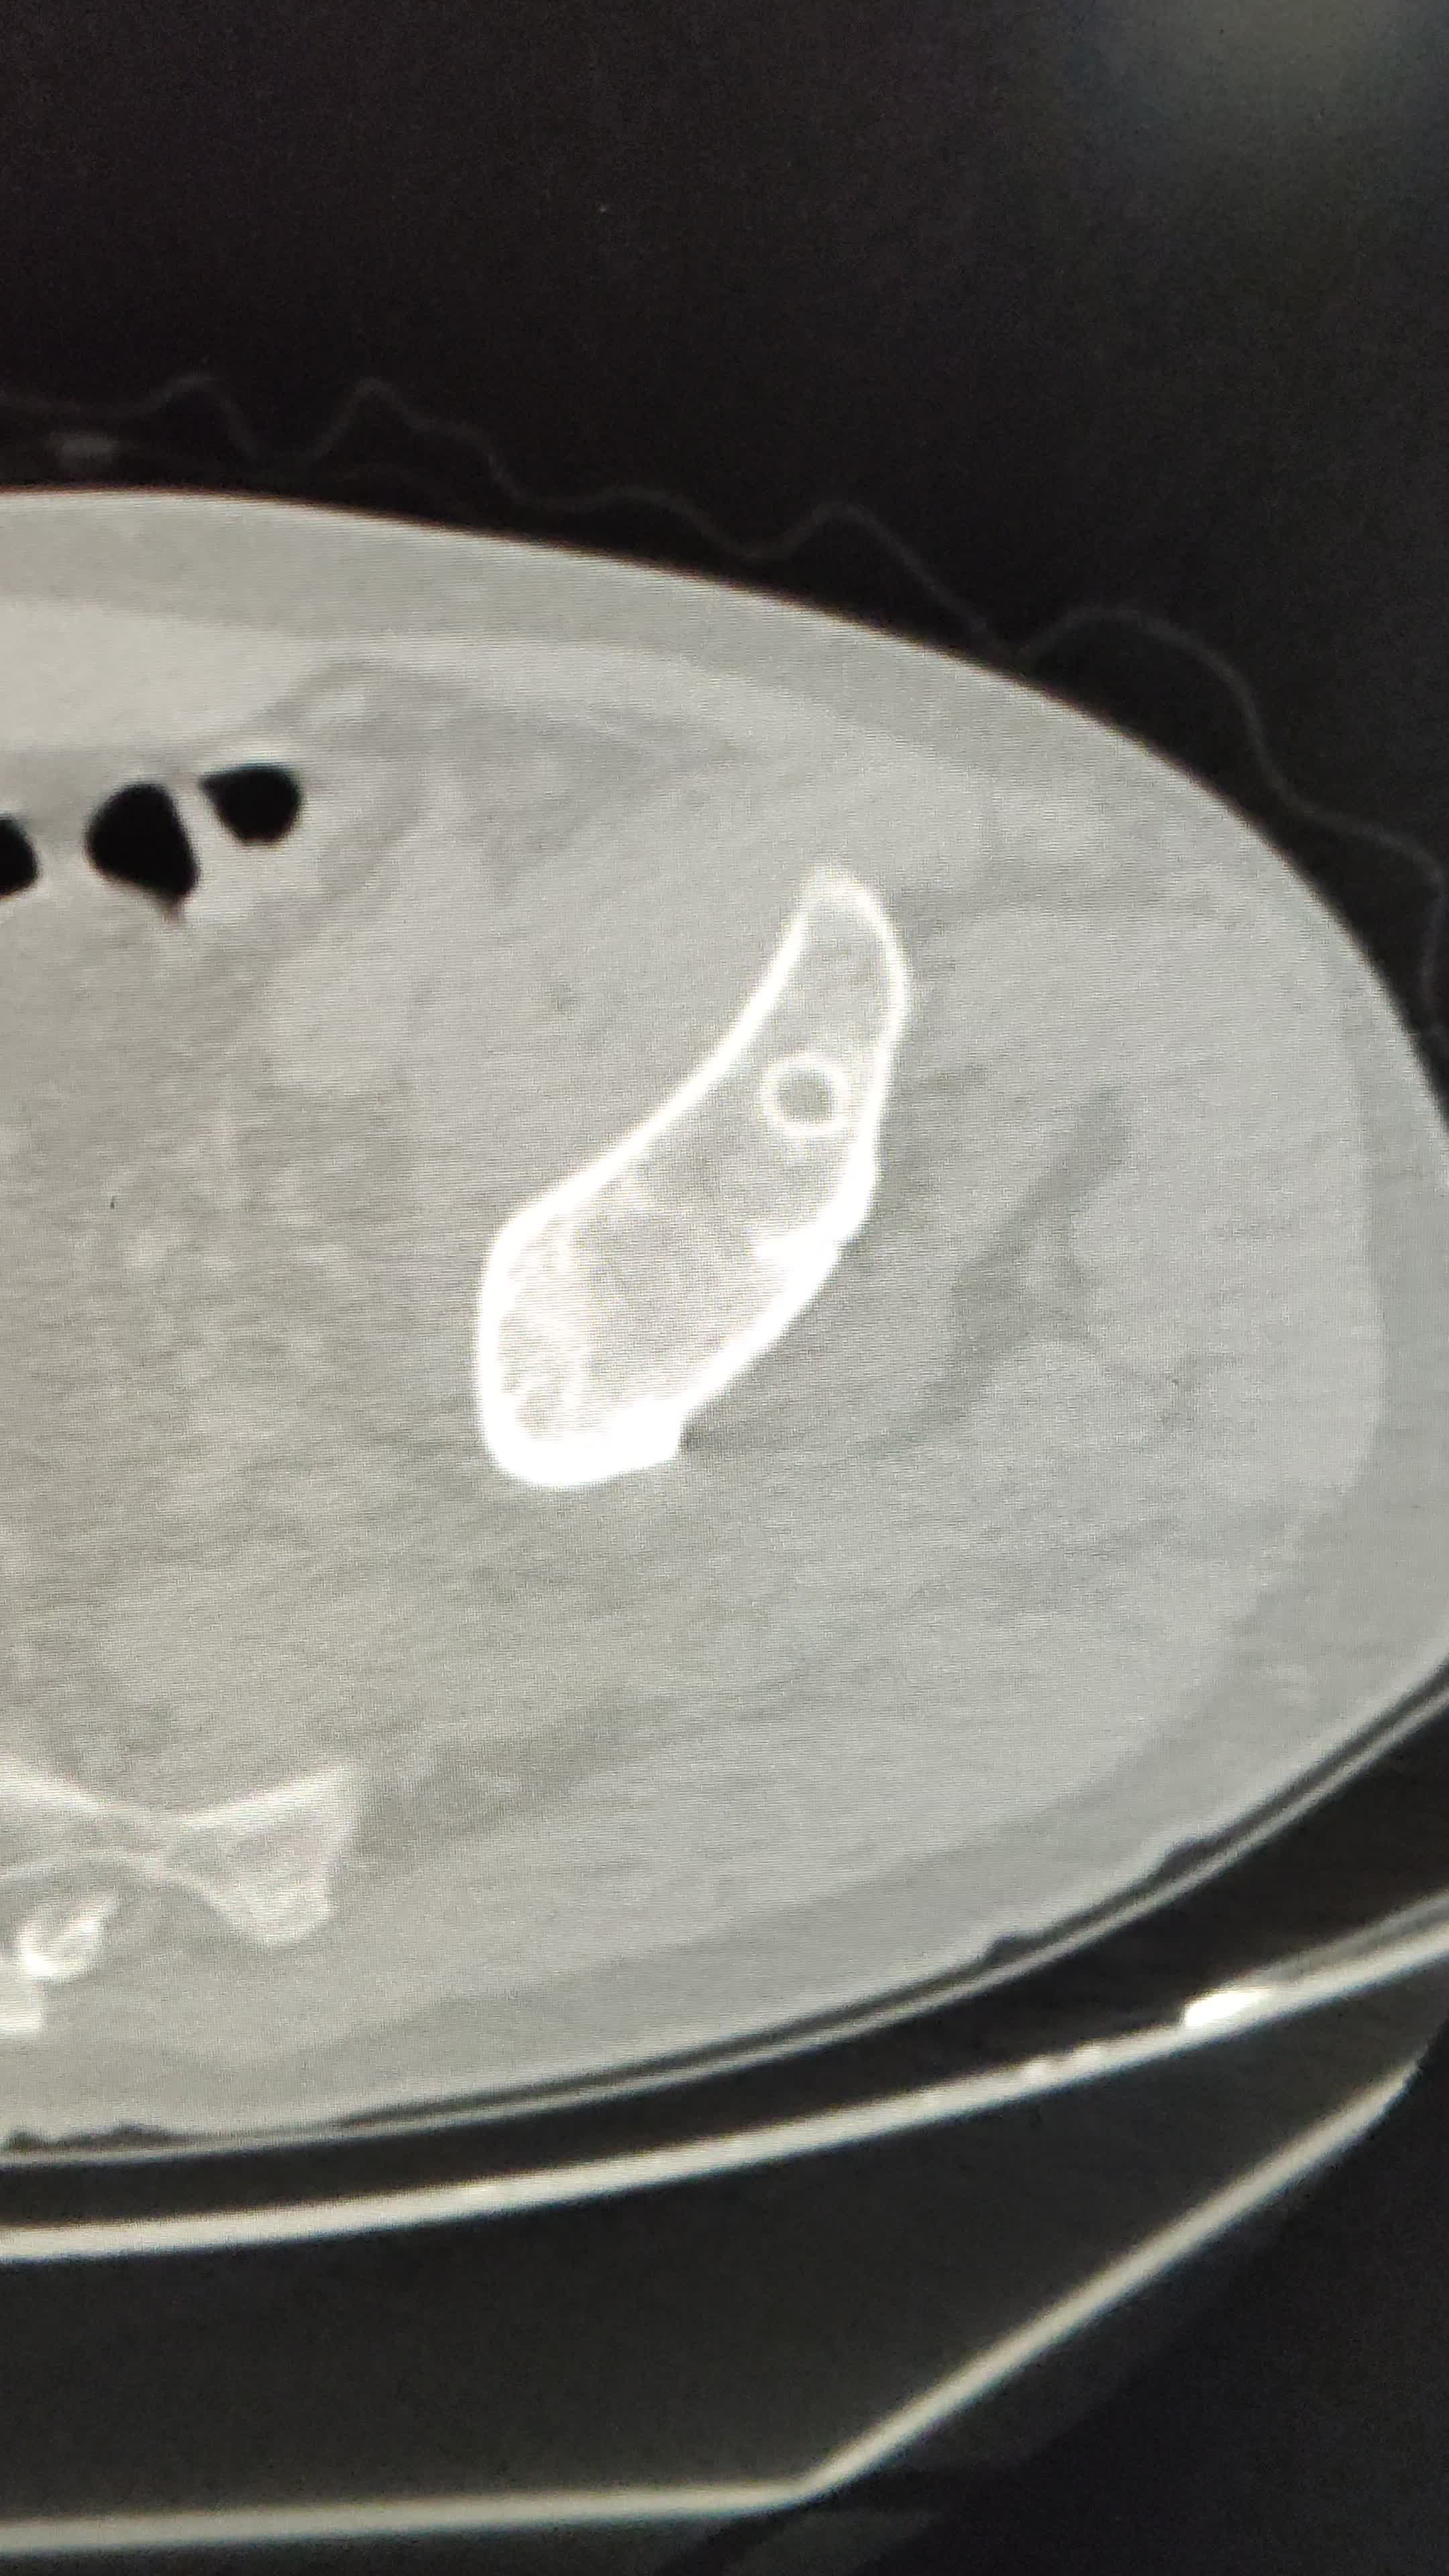

髋关节置换术后12年,大腿前内侧窦道1年,再发2周

mmHg。左大腿上段前内侧可见2处直径约1cm的窦道,周围皮肤色素沉着,轻度红肿,轻度压痛。左髋关节后侧见长约15cm手术瘢痕,愈合良好,无红肿及压痛。左髋关节活动尚可。

辅助检查:近期的ESR(血沉) 32mm/h↑,hsCRP(高敏C反应蛋白) 25.55mg/L↑,PCT(降钙素原)0.03ng/ml,正常。血常规正常。X线片及CT是近期的。12年前的影像资料缺失。